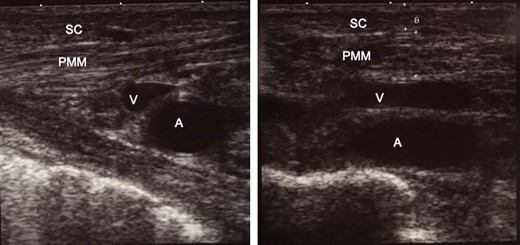

Ultrasound-guided TLA administration was performed on the left upper precordium. TLA solution (430 mL normal saline, 20 mL sodium bicarbonate, 50 mL 1% xylocaine, and 0.5 mg epinephrine) was infused around the axillary vein and artery, subpectoral area, pectoralis major, and subcutaneous tissue along the planned-incision line (Fig. 1). A total of 75 mL TLA solution was infused under ultrasound and X-ray guidance below the pectoralis major, where the pocket for the pacemaker was to be created (Fig. 2).

Intra-operative ultrasound examination for confirming the position of organs before infusion of tumescent local analgesia solution. The thickness of the subcutaneous tissue, 2.6 mm; and pectoralis major muscle, 5.6 mm. (a) The right side of the picture is the superior (head) side of the patient. (b) The right side of the picture is the right side of the patient. SC, subcutaneous tissue; PMM, pectoralis major muscle; V, axillary vein; A, axillary artery.